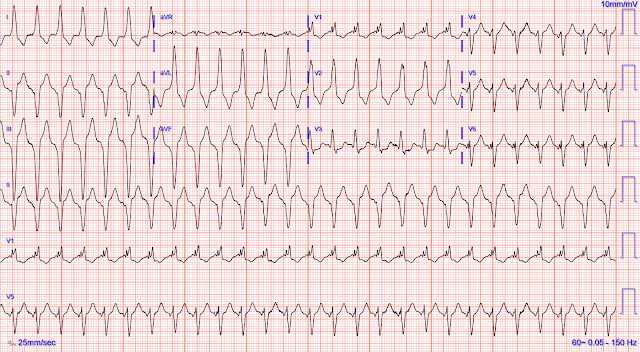

Без контекста, что, по-вашему, это за ритм?

Комментарий Смита: тахикардия с широкими комплексами.

— ЭКГ № 1 — (первоначальная ЭКГ, показанная доктором Мейерсом):

==============================

С образовательной точки зрения я считаю, что выбор доктора Мейерса был превосходным, который начал демонстрацию сегодняшнего случая с показа сначала 3-й ЭКГ (хотя эта ЭКГ, которую я разметил на рисунке 1, была записана после ЭКГ № 2 и ЭКГ № 3, и они показаны на рисунке 2 ниже).

Скорая помощь должна быть уверена, что ЭКГ № 1 почти наверняка говорит о ЖТ.

- Нам сказали, что ЭКГ на рисунке 1 принадлежит остро больной пожилой женщине с сопутствующими заболеваниями. Ритм на этой ЭКГ — регулярная тахикардия с широкими комплексами и частотой ~160/мин, без явных признаков предсердной активности. Зная это — прежде чем мы даже начнем рассматривать конкретные особенности этой ЭКГ, нам нужно помнить, что статистическая вероятность того, что этот ритм является ЖТ, приближается к 90%. В результате — наше мышление заключается не в том, чтобы определить, «может ли» этот ритм быть ЖТ — а скорее в том, что нам нужно подразумевать ЖТ (и лечить соответствующим образом), если мы не сможем окончательно доказать обратное.

- Хотя может возникнуть соблазн интерпретировать небольшие отрицательные отклонения, отмеченные СИНИМИ стрелками в длинной полосе ритма отведения V5, как зубцы P — это не зубцы P. Как показывают двойные КРАСНЫЕ стрелки — комплекс QRS в каждом из отведений от конечностей начинается с едва заметного смазывания. Таким образом, параллельные СИНИЕ временные линии показывают, что это начальное отрицательное отклонение в отведении V5 является частью QRS.

- КЛЮЧЕВОЙ момент: Когда вы видите отклонения, которые «выглядят» как синусовые зубцы P в одном или двух отведениях, но вы не видите ничего похожего на синусовый зубец P ни в отведении II, ни в отведении V1 — тогда эти отклонения, которые вы видите в этих других отведениях (например, отрицательные отклонения здесь, в отведении V5), не являются синусовыми зубцами P!

- «12 отведений лучше, чем одно» — и умелое использование одновременно записанных отведений может быть бесценным. Например — параллельная ЗЕЛЕНАЯ временная шкала говорит нам, что похожее небольшое отрицательное отклонение также появляется в начале комплекса QRS в отведениях V4 и V6. Это отрицательное отклонение является зубцом Q — и оно удивительно широкое для своего крошечного размера, а за ним следует зазубренный (фрагментированный) комплекс rsr'S в отведении V6. По моему опыту, наблюдение удивительно широких, последовательных зубцов Q в серии грудных отведений (что мы видим в отведениях V4, V5, V6) — это «подсказка», что ритм почти наверняка будет ЖТ.

- Возвращаясь к отведениям от конечностей на рисунке 1 — во время этого ритма с широкими комплексами наблюдается экстремальное отклонение оси во фронтальной плоскости (которое мы легко распознаем по обнаружению полностью отрицательных комплексов QRS в каждом из нижних отведений). Это еще одна «подсказка» к 98+% вероятности того, что ритм является ЖТ (за отсутствием редкого исключения в виде заметно искаженной базовой линии с идентичной морфологией).

- Подчеркну: критерий «экстремального» отклонения оси во фронтальной плоскости во время ритма с широкими комплексами не работает, если только QRS не полностью отрицателен либо в отведении I, либо в отведении aVF. Но особенно учитывая начальное нечеткое снижение комплексов QS в нижних отведениях на рисунке 1 — «картина», которую мы здесь видим, почти никогда не наблюдается при наджелудочковых ритмах.

- Есть ли относительная «задержка» в начальном отклонении QRS? Ритмы СВТ, как правило, демонстрируют более быстрые начальные векторы деполяризации — потому что наджелудочковая деполяризация обычно начинает свой путь к желудочкам, проходя по установленным путям проведения. Заметным исключением из этого общего правила является случай, когда есть ДП (дополнительный путь), который обходит АВ-узел (т. е. у пациента с WPW). Тем не менее — «относительная задержка» в начальной части комплекса QRS в нескольких отведениях более соответствует ЖТ. И — ни в одном отведении на рисунке 1 нет быстрой начальной деполяризации комплекса QRS, таким образом, еще одна особенность, указывающая на ЖТ. (Запомните этот критерий! — поскольку мы применим его на мгновение, когда еще раз посмотрим на рисунок 2 ниже).

Но прежде чем перейти к рисунку 2 — рассмотрим последний критерий: есть ли сходство с какой-либо известной формой нарушения проводимости?

- На ЭКГ № 1 — может показаться, что комплекс QRS в отведении V1 напоминает морфологию БПНПГ. Но так ли это? Как выделено в пунктирном ЗЕЛЕНОМ овале — морфология QRS в отведении V1 представляет собой rsR'R'' — или действительно странную морфологию, совсем не похожую на типичные трехфазные rSR', характерную для БПНПГ. И хотя у пациентов с сопутствующими заболеваниями сердца часто проявляются вариации этой типичной трехфазной морфологии — в отведении V1 имеется действительно странная морфология QRS.

- В некотором роде картина в отведениях от конечностей напоминает БЛНПГ (а не БПНПГ). Поэтому — морфология QRS на рисунке 1 и близко не похожа ни на одну известную форму дефекта проводимости.

ЗАКЛЮЧЕНИЕ: Я рассмотрел вышеперечисленные особенности ЭКГ № 1 с определенным «замедлением». Тем не менее, с практикой применения этих особенностей — для этой записи вывод о 98+% вероятности ЖТ должен быть получен в течение нескольких секунд!

Рисунок 1: Это первая ЭКГ, показанная доктором Мейерсом в сегодняшнем случае. Насколько ВЫ были уверены, что это ЖТ?